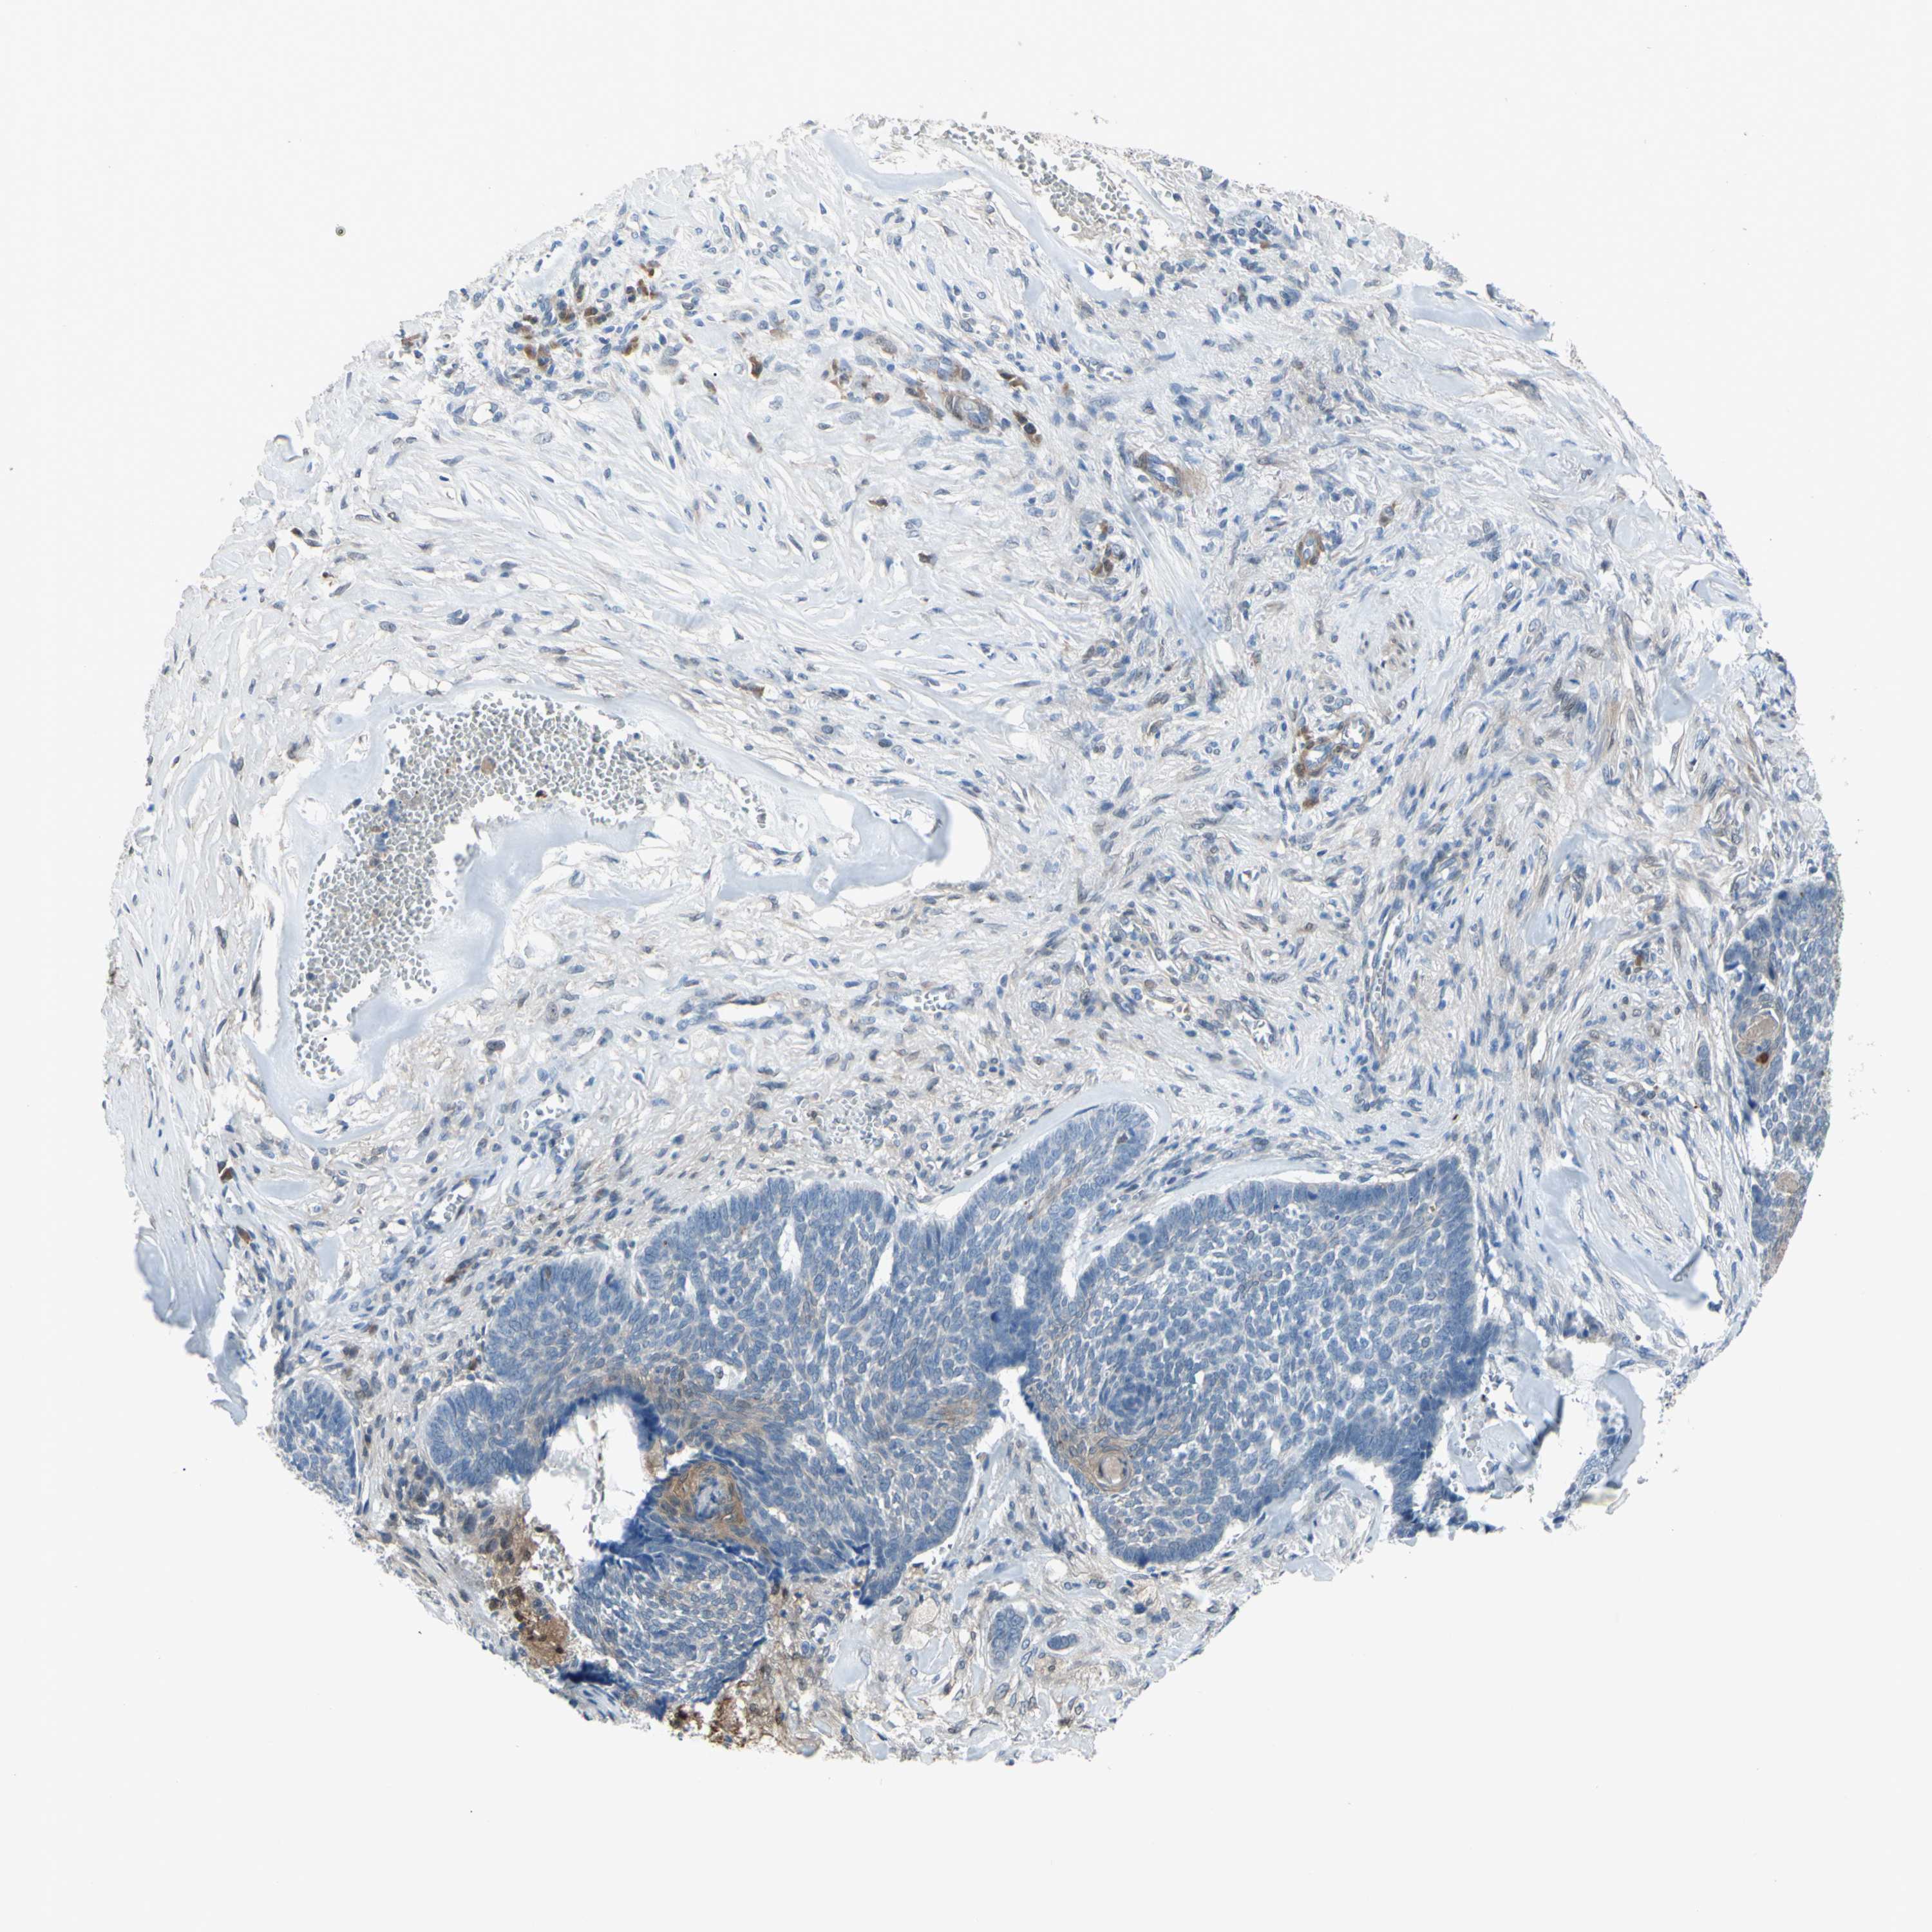

Basal cell and squamous cell cancer

SKIN CANCER - Protein expressioni

A mouse-over function shows sample information and annotation data. Click on an image to view it in a full screen mode. Samples can be filtered based on level of antibody staining by selecting one or several of the following categories: high, medium, low and not detected. The assay and annotation is described here.

Each image is clickable and will lead to virtual microscopy that enables deeper exploration of all samples and also displays staining intensity scores, fraction scores and subcellular localization as well as patient and tissue information for each sample.

Antibody CAB009208

Staining

High

Medium

Low

Not detected

Intensity

Strong

Moderate

Weak

Negative

Quantity

>75%

75%-25%

<25%

None

Location

Nuclear

Cytoplasmic/membranous

Cytoplasmic/membranous,nuclear

Squamous cell carcinoma, NOS

Basal cell carcinoma